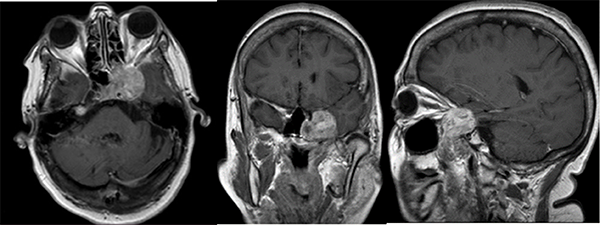

La resonancia magnética nuclear (RMN) evidenció una lesión a nivel del seno cavernoso izquierdo, la cual impresionaba proyectarse sobre el cavum, la fisura orbitaria y sector lateral izquierdo de la silla turca. Presentaba realce heterogéneo posterior a la inyección de contraste endovenoso, tenía un aspecto polilobulado y un diámetro máximo de 49x32x30 mm (CCxTxAP). (Fig 1.)